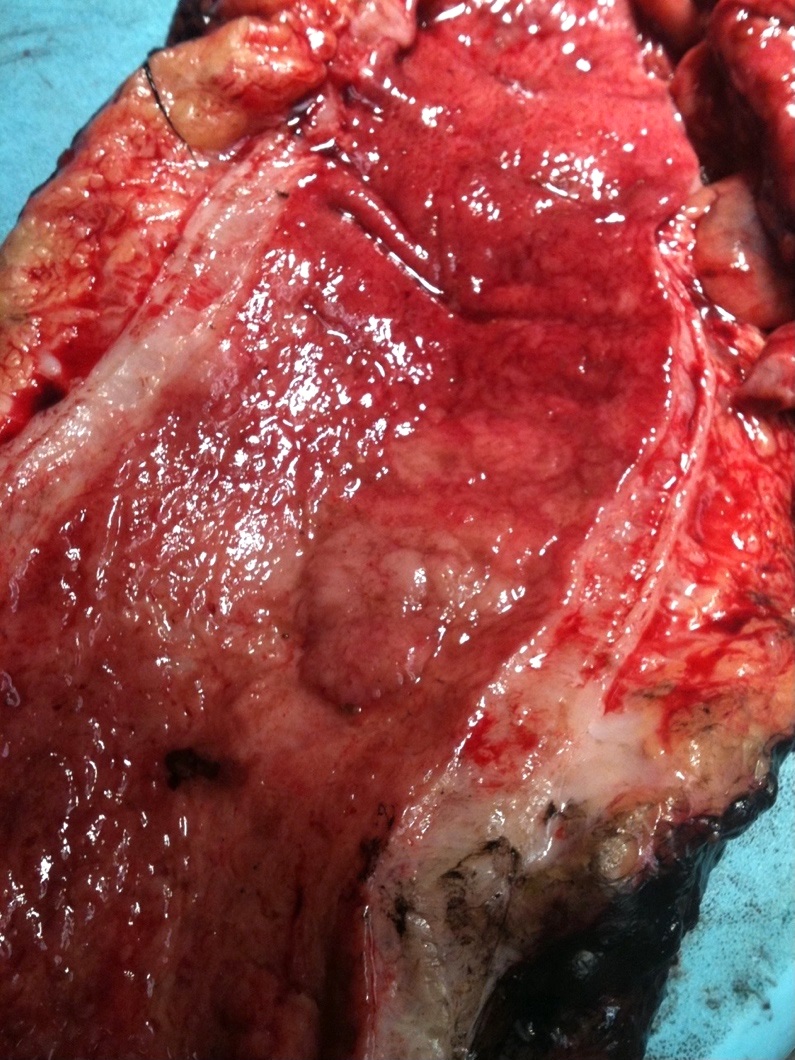

Gross description

- Can be macroscopically (endoscopically) unapparent

- Can be polypoid (pedunculated or sessile) or nonpolypoid (superficially elevated, flat or depressed)

Gross images